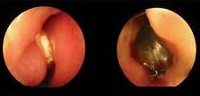

Инородное тело носа. Случайно попавший в полость носа чужеродный объект - бусинка, ягодная косточка, семечка, мелкая деталь игрушки, комар или другое насекомое, кусочек дерева, пластмассы, еды, ваты или бумаги. Инородное тело носа может быть бессимптомным. Но чаще оно проявляется болью, односторонней заложенностью носа и выделениями из пораженной половины носа. Диагностировать инородное тело носа помогают данные анамнеза, результаты отоларингологического осмотра и риноскопии, данные КТ и рентгенографии. Лечение инородного тела носа состоит в его как можно более раннем устранении путем выдувания, эндоскопического или хирургического удалении.

В большинстве случаев инородное тело носа может быть диагностировано отоларингологом на основании анамнеза, результатов осмотра полости носа и риноскопии. Затруднения диагностики возникают у детей младшего возраста, в анамнезе которых может отсутствовать указание на попадание инородного объекта в нос. Трудно обнаруживается длительно существующее инородное тело носа. В ходе риноскопии оно может не визуализироваться из-за выраженного отека, воспалительных изменений слизистой или образовавшихся грануляций. В таких случаях для обнаружения инородного тела носа применяют ощупывание металлическим зондом. Однако это позволяет выявить только плотные инородные объекты.